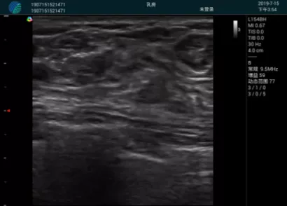

清晰顯示腺體內(nèi)低回聲快影,邊界清晰,包膜較光滑

確定進(jìn)針路徑并實(shí)時監(jiān)測抽吸針與腫塊位置關(guān)系

抽吸針進(jìn)入腫塊內(nèi)部進(jìn)行旋切

抽吸過程中可見腫塊明顯縮小,并根據(jù)腫塊位置改變針道位置

抽吸旋切后再進(jìn)行超聲復(fù)查,原腫塊區(qū)域未見殘留組織及出血